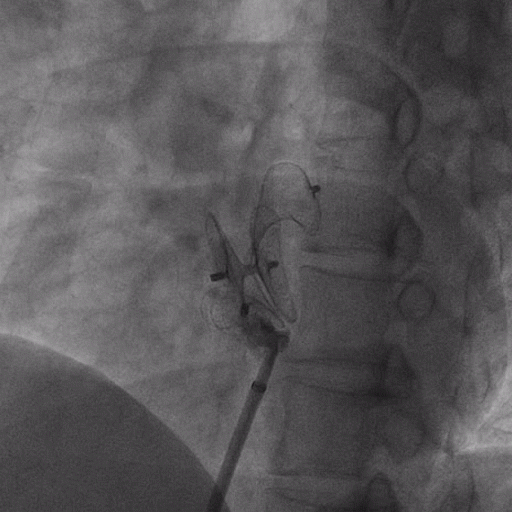

在獲得患者同意后,1月12日,尚福軍主任為患者進(jìn)行了PFO封堵術(shù)。術(shù)中造影可見(jiàn)封堵器殘余漏,尚福軍主任用精湛的技藝,順利通過(guò)封堵器殘余漏裂縫,將右心導(dǎo)管從右房送入左房,且順利到達(dá)肺靜脈;遂行卵圓孔未閉封堵術(shù)后殘余漏再次封堵;且完美釋放PFO封堵器,可見(jiàn)兩封堵器呈“馬蹄蓮”狀,再次術(shù)中造影未見(jiàn)殘余漏。

術(shù)后,小鞏生命體征平穩(wěn)。相關(guān)檢查顯示正常,且術(shù)后完善心臟彩超及發(fā)泡試驗(yàn),可見(jiàn)封堵器位置良好,未見(jiàn)右向左分流,發(fā)泡試驗(yàn)陰性。